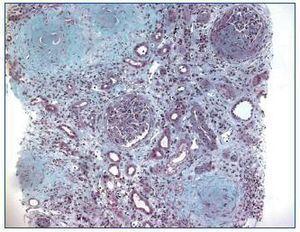

Renal ultrasound revealed normal sized kidneys, cortical hyperechogenicity, normal parenquimatous differentiation, and no hydronephrosis. Computed tomography (CT) of the face disclosed mucous thickening of the frontal, ethmoid, sphenoid and maxillary sinuses lining, and CT of the chest revealed ground-glass opacities widely spread across both lungs. Lower limbs electromiogram revealed severe multiple mononeuritis. Bone marrow biopsy disclosed eosinophilic hypercellularity and no morphologic abnormalities. A renal biopsy was performed and showed CGN with linear deposition of IgG along the glomerular capillaries (Figure 1 and figure 2). Serology for lupus (antinuclear, anti-double strand deoxyribonucleic acid, anti-Smith, extractable nuclear and anti-ribonucleoprotein antibodies) was negative. Serum C3, and C4 were on the normal range. Serology for human immunodeficiency virus types 1 and 2, hepatitis B, hepatitis C was also negative. Indirect immunofluorescence assay detected perinuclear ANCA (p-ANCA) (90 U/ml) and enzyme-linked immunosorbent assay (ELISA) revealed MPO specificity. Anti-GBM antibodies in serum (169 U/ml) were detected by direct ELISA. According to these, the diagnosis of CGN with double-positivity for anti-GBM antibodies and MPO-ANCA was established. She underwent intermittent hemodialysis, and immunosupressive therapy with metilprednisolone (15 mg/kg/day, 3 days, IV) followed by oral prednisone (1 mg/kg/day), cyclophosphamide (750 mg/m2, monthly, IV), and plasma exchange with daily exchange of one volume of plasma for 5% human albumin for 14 days was initiated. She also received red blood cell transfusions. Two weeks later, the patient was asymptomatic, recovered diuresis, and improved renal function. At hospital discharge (day 38), uremia and creatinemia were 148 mg/dl and 2.5 mg/dl, respectively, and hemoglobin was 10.9 g/dl. She had no clinical or laboratorial evidence of disease relapse, and she remains out of dialysis.

Figure 1. Kidney biopsy showing crescentic glomerulonephritis (Masson trichrome, x100).